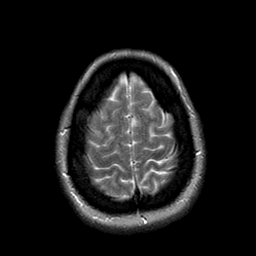

Cerebral hemorrhage, MR Study mr-t2 -- Slice #20

[Home][Help][Clinical] Slice 20